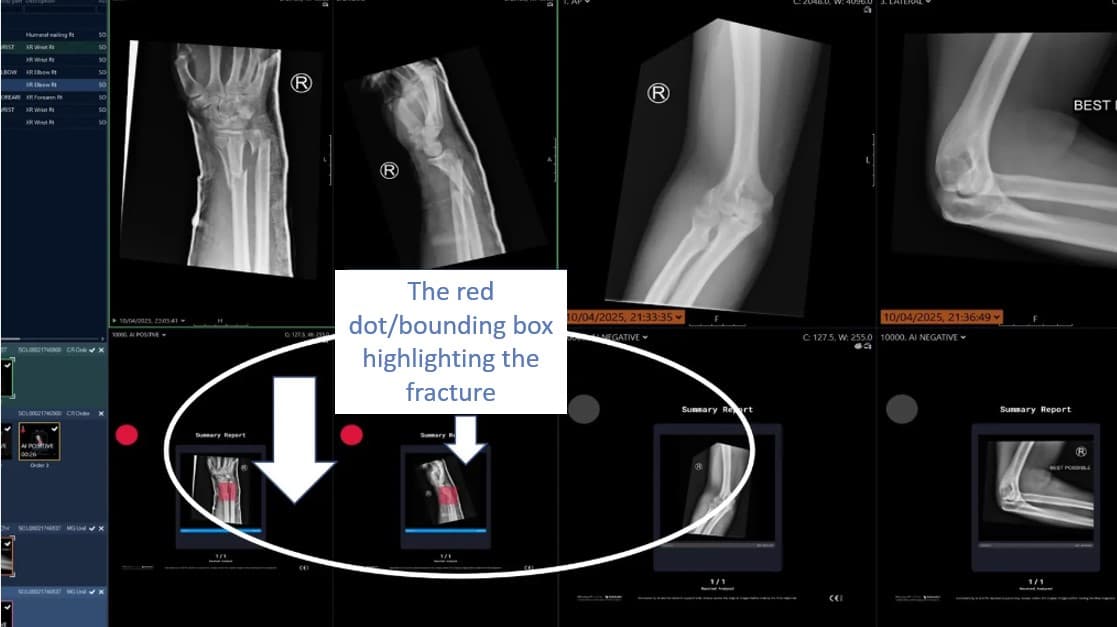

We develop AI platforms, data science and tools that support clinicians and benefiting patient experience.

With the help of our AI expert consortium partners, we have developed sophisticated artificial intelligence algorithms by the NHS for the NHS – across Population Health, research and patient pathways.